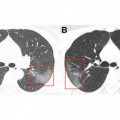

Ինչպիսի տեսք ունեն կորոնավիրուսով հիվանդների թոքերը (լուսանկար)